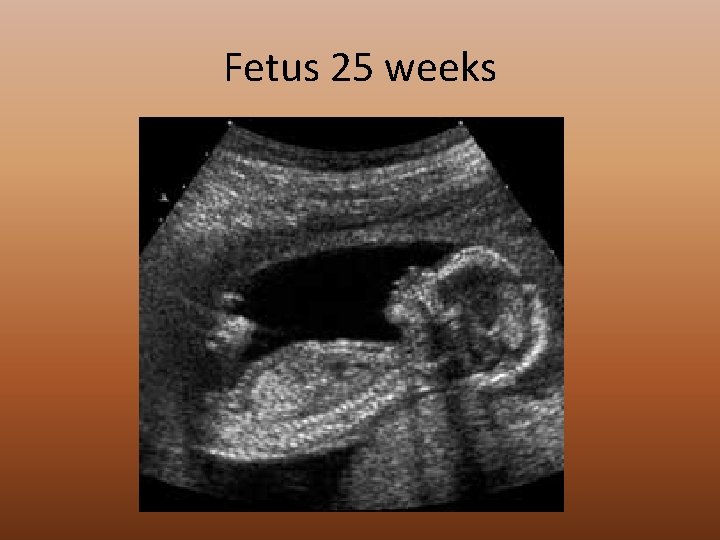

Fetus 25 weeks

Fetal Development First Trimester (0 -12 weeks) • Organ systems begin to develop and form. Bone cells form. Second Trimester (12 -24 weeks) • Rapid growth from 12 -16 weeks. Third Trimester (24+ weeks) • Continued growth, especially of brain. Fat begins to deposit at 32 weeks to keep baby warm at birth.